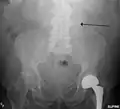

A ruptured AAA with an open arrow marking the aneurysm and the closed arrow marking the free blood in the abdomen -